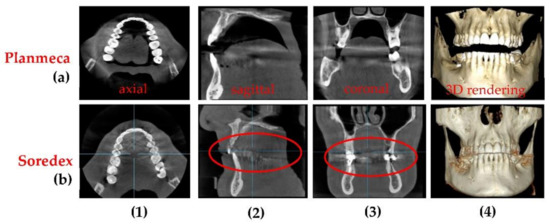

3.4. Differences Between the Planmeca and the Soredex System

| Diameter of Image Base (mm) | Image Height (mm) | Voxel Side (µm) | Anode Voltage (kV) | Current Intensity (mA) | Exposure Time (s) | ||

|---|---|---|---|---|---|---|---|

| Before | 80 | 200 | 84 | 14 | 12.057 | 1170 | |

| After | 80 | 150 | 90 | 14 | 5.072 | 691 |

| Radiograph | Characteristics | Planmeca | Soredex | |

|---|---|---|---|---|

| Panoramic | Anode voltage (kV) | 68 to 73 | 70 to 75 | |

| Current intensity (mA) | 8 to 11 | 8 to 11 | ||

| Exposure time (s) | 14.990 | 16 | ||

| DAP (mGy×cm2) | 97 to 117 | 175 to 250 | ||

| Effective Dose (µSv) | 7.8 to 9.2 | 14 to 20 | ||

| Pixel side (µm) | 127 | 100 | ||

| Total 3D CBCT | Anode voltage (kV) | 90 | 85 to 90 | |

| Current intensity (mA) | 11 to 14 | 6 to 10 | ||

| Exposure time (s) | 5 | 6 to 9 | ||

| DAP (mGy×cm2) | 691* | 749.5 ** | ||

| Effective Dose (µSv) | 86.4* | 93.7 ** | ||

| Voxel side (µm) | 150 | 200 | ||

| Base diameter (mm) | of the investigated volume | 110 | 150 | |

| Height (mm) | 80 | 80 | ||

| Segmental 3D CBCT | Anode voltage (kV) | 90 | 85 to 90 | |

| DAP (mGy×cm2) | 329 * | 140 to 300 ** | ||

| Effective Dose (µSv) | 32.9 to 49.35 | 20 to 30 ** | ||

| Base diameter (mm) | of the investigated volume | 50 | 50 | |

| Height (mm) | 50 | 50 | ||

| Maxillary/mandible 3D CBCT | Anode voltage (kV) | 90 | 85 to 90 | |

| DAP (mGy×cm2) | 429 * | 400 ± 50 ** | ||

| Effective Dose (µSv) | 42.9 to 64.35 | 40 ± to 60 ± ** | ||

| Base diameter (mm) | of the investigated volume | 110 | 61 | |

| Height (mm) | 50 | 78 | ||

| Method | Equipment | Advantages and Disadvantages |

|---|---|---|

| Panoramic | Planmeca and Soredex | Radiation dose is almost 50% smaller for Planmeca. Resolution is lower (127 µm) for Planmeca than for Soredex (100 µm). Images produced by Soredex have a lower contrast and sharpness even if they have better resolutions. |

| 3D CBCT | Planmeca and Soredex | Smaller exposure time (5 versus 9 s), smaller radiation dose (with at least 10 µSv), and smaller voxel side (with 25%) for Planmeca, which means better resolution, contrast, and image quality. The covered volume is larger for Soredex. |

| OCT | SS-OCT | Better resolution, usually, around 10 µm axial (i.e., in depth), but it can be as low as 2 µm [17]. Lateral resolution (i.e., on the sample surface) is adjustable by galvanometer scanners programming; in this study it was set to 6 µm (corresponding to 500 B-scans for a scan length of 3 mm) or to 10 µm (for 500 B-scans per 5 mm). In contrast, the smallest achievable linear resolution (on each spatial direction) for 3D CBCT is 75 µm. Low penetration depth, but no ionizing radiation for OCT. The maximum volume scanned with OCT is 5 × 5 × 2 mm, while for radiography the volume corresponds at least to a cylinder with the base diameter of 50 mm and the height of 50 mm. |